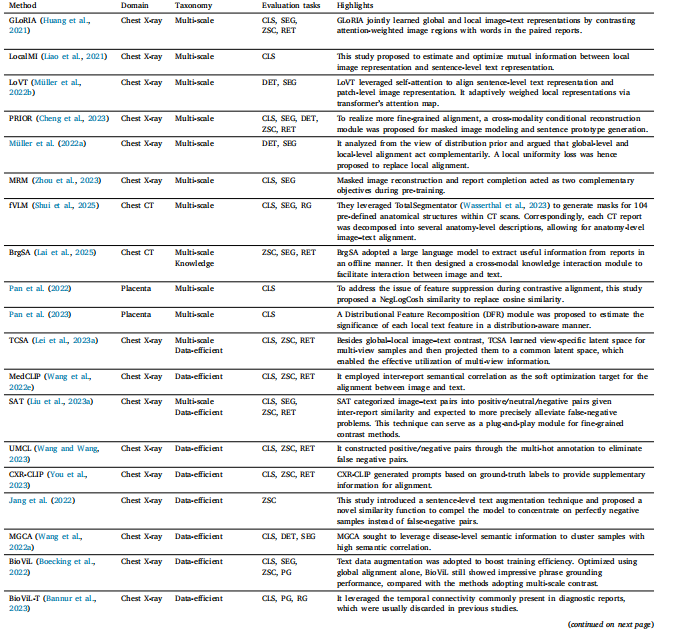

Table 2Overview of representative studies focusing on improving CLIP pre-training framework. CLS: classification; ZSC: zero-shot classification; SEG: segmentation; DET: detection; RET:retrieval; VQA: visual question answering; PG: phrase grounding; RG: report generation; ITC: image–text classification; SP: survival prediction.

表2 专注于改进对比语言-图像预训练模型(CLIP)预训练框架的代表性研究概述。CLS:分类;ZSC:零样本分类;SEG:分割;DET:检测;RET:检索;VQA:视觉问答;PG:短语定位;RG:报告生成;ITC:图像-文本分类;SP:生存预测。